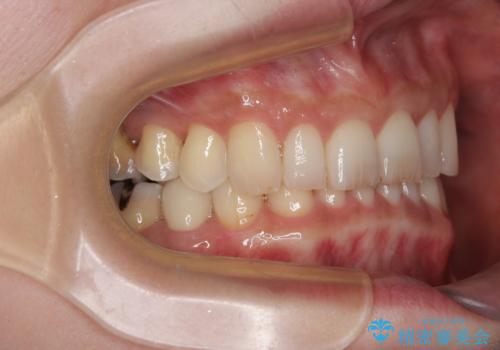

その後、オールセラミッククラウンにて補綴治療を行う予定でしたが、処置した歯以外にも治療が必要と思われる歯があったり、デコボコした歯列も気になるとのことで、患者様希望によりインビザラインにてマウスピース矯正を行うこととしました。

まずは矯正治療前に必要なむし歯処置を行い、その後矯正治療を行ってから、最後にオールセラミッククラウンなどで補綴治療を行うこととしました。

咬合力が非常に強く、全体的に歯が擦り減っている状態であったので、理想的な咬み合わせを達成することは難しく、また咬合力が強い方のマウスピース矯正は、思い通りに動かないことがあるため、ワイヤー矯正の方が望ましいように思えました。

治療途中で2年強、体調を崩されて通院ができなくなってしまったため、必ず通院が必要なワイヤー矯正ではなく、マウスピース矯正で結果的には無事に治療を終えることができました。